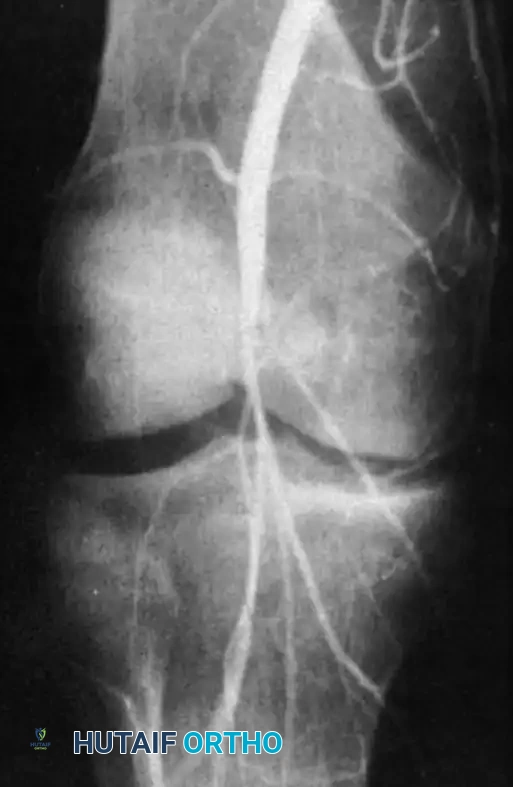

Arteriography: Femoral arteriography or CT Angiography is indicated for any patient with questionable circulation, an ABI < 0.90, or absent peripheral pulses before or after reduction.

Fig. 43-148: Femoral arteriogram in a patient with a knee dislocation, demonstrating abrupt occlusion of the popliteal artery requiring emergent vascular bypass.